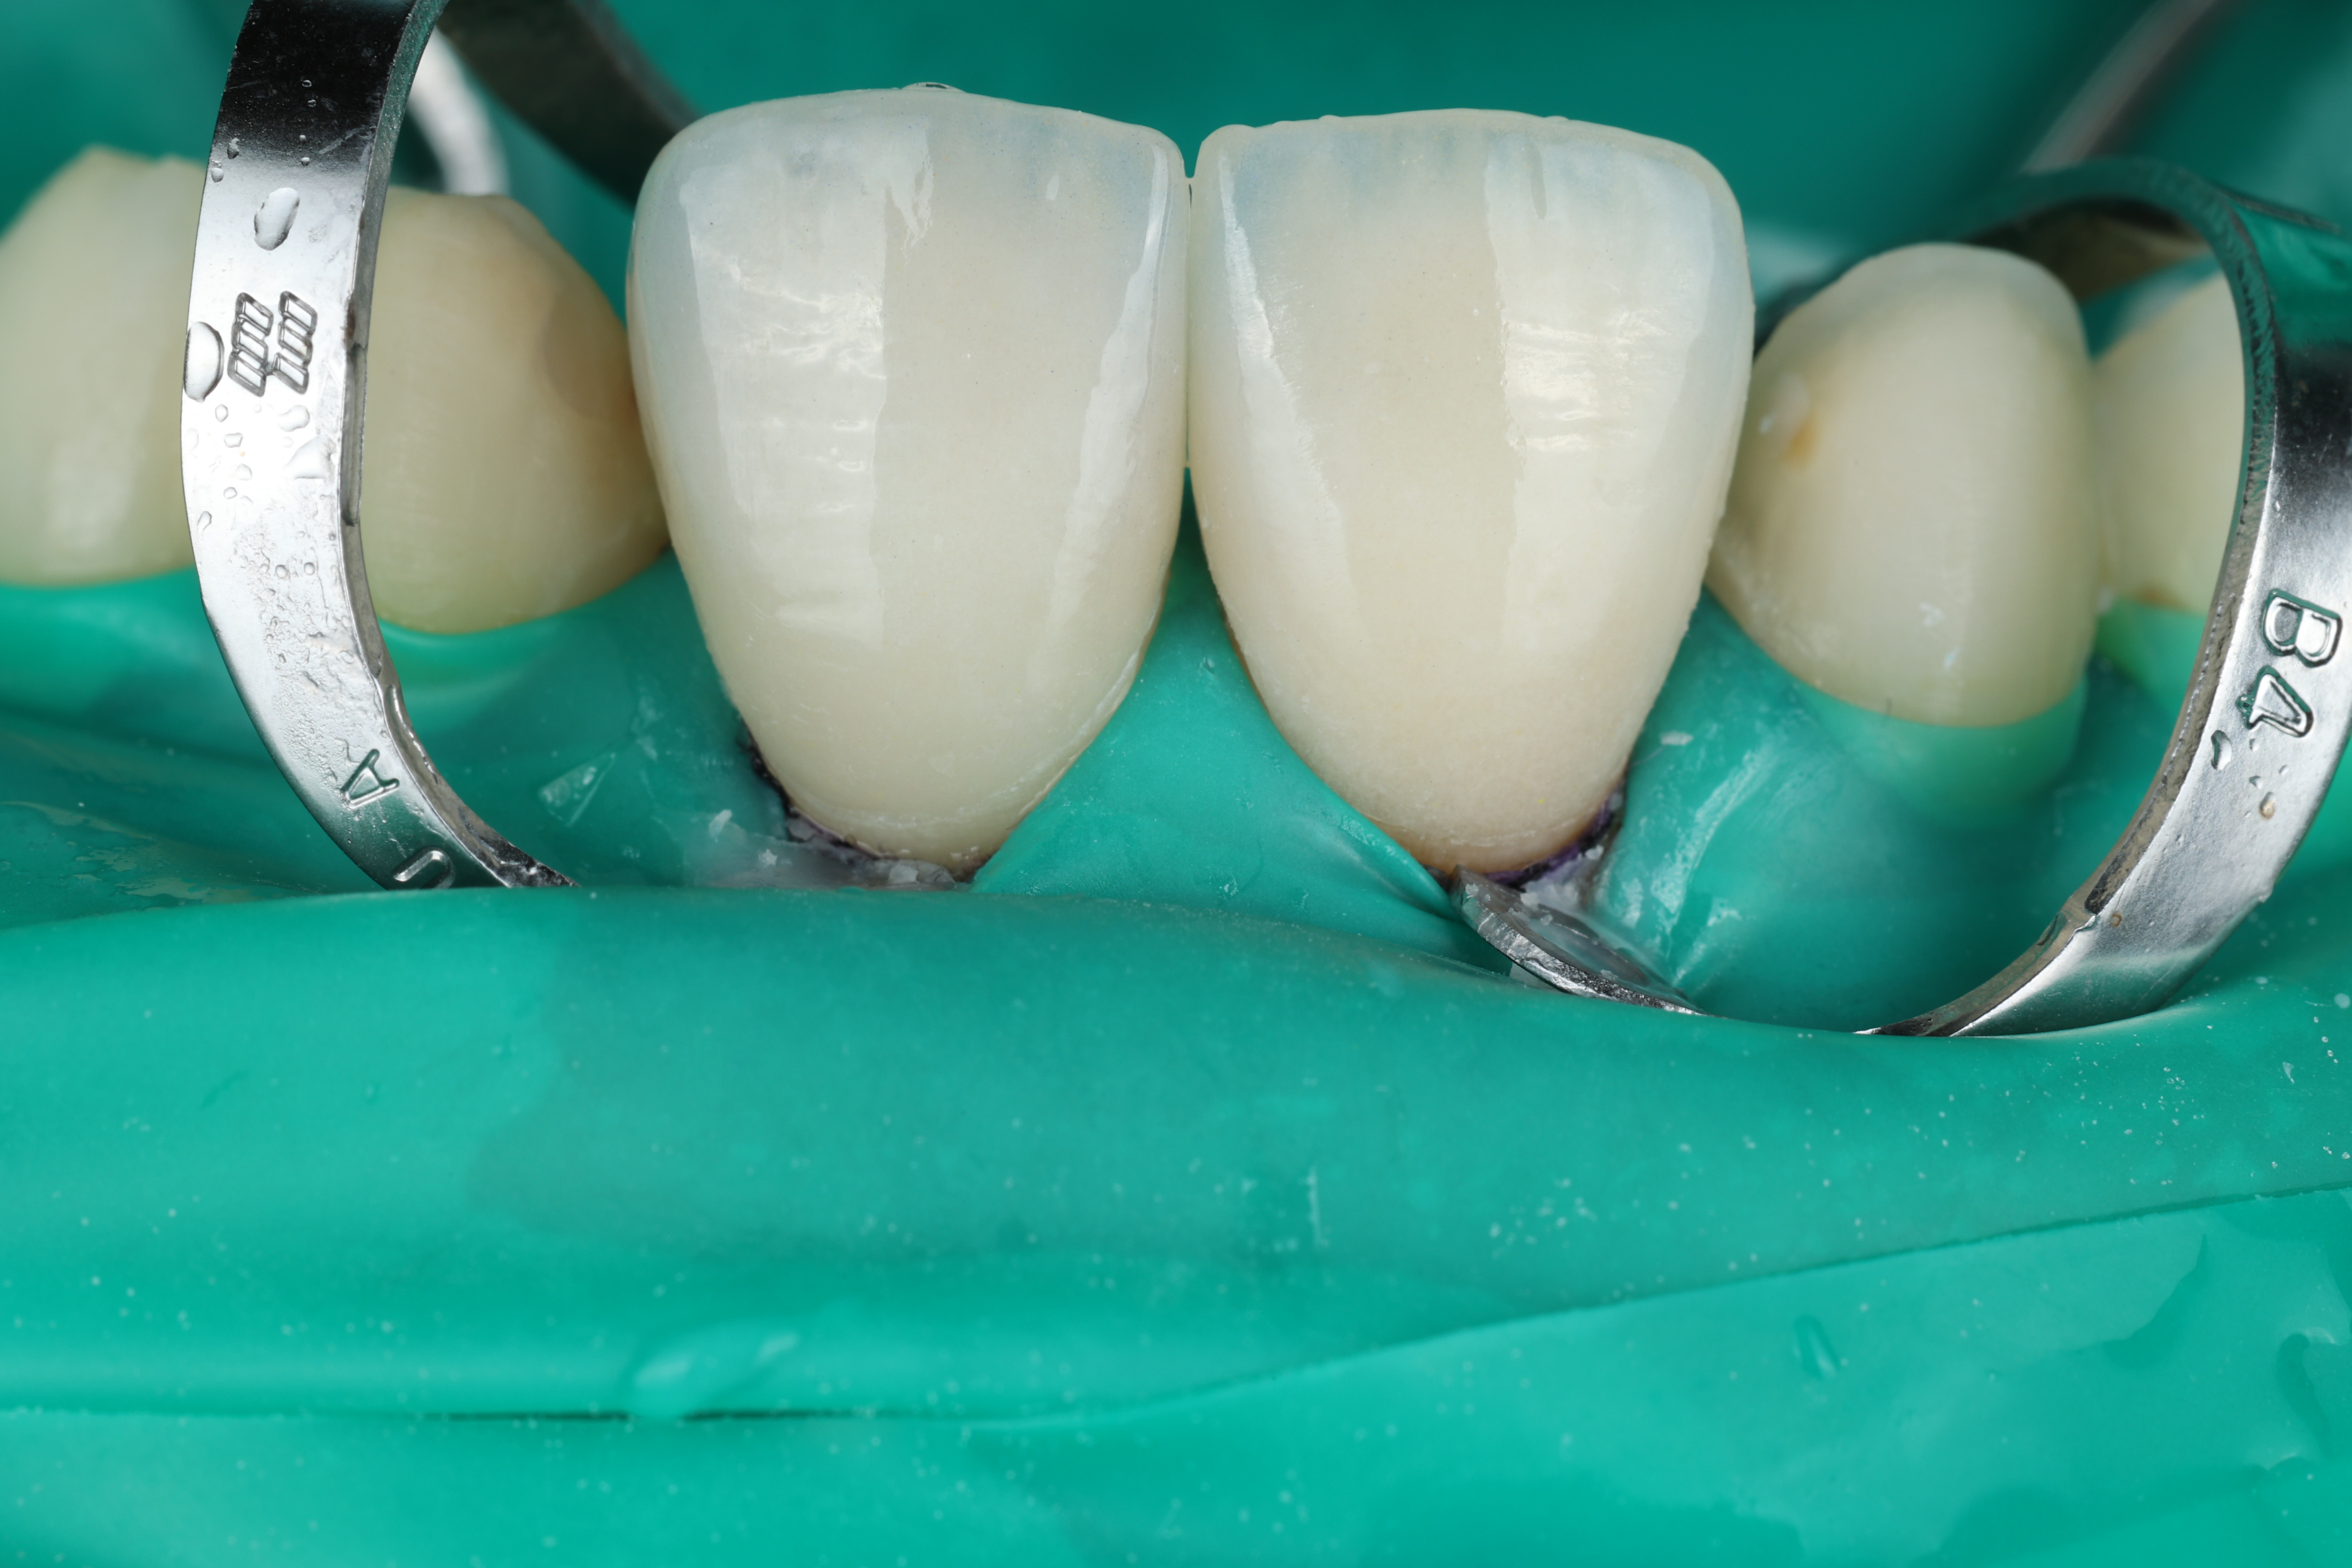

الخطوة 3: التثبيت الدقيق

تم تثبيت جميع الفينيرات باستخدام العازل المطاطي لضمان الجفاف التام، مما يضمن ثباتًا طويل الأمد وتلاصقًا مثاليًا.